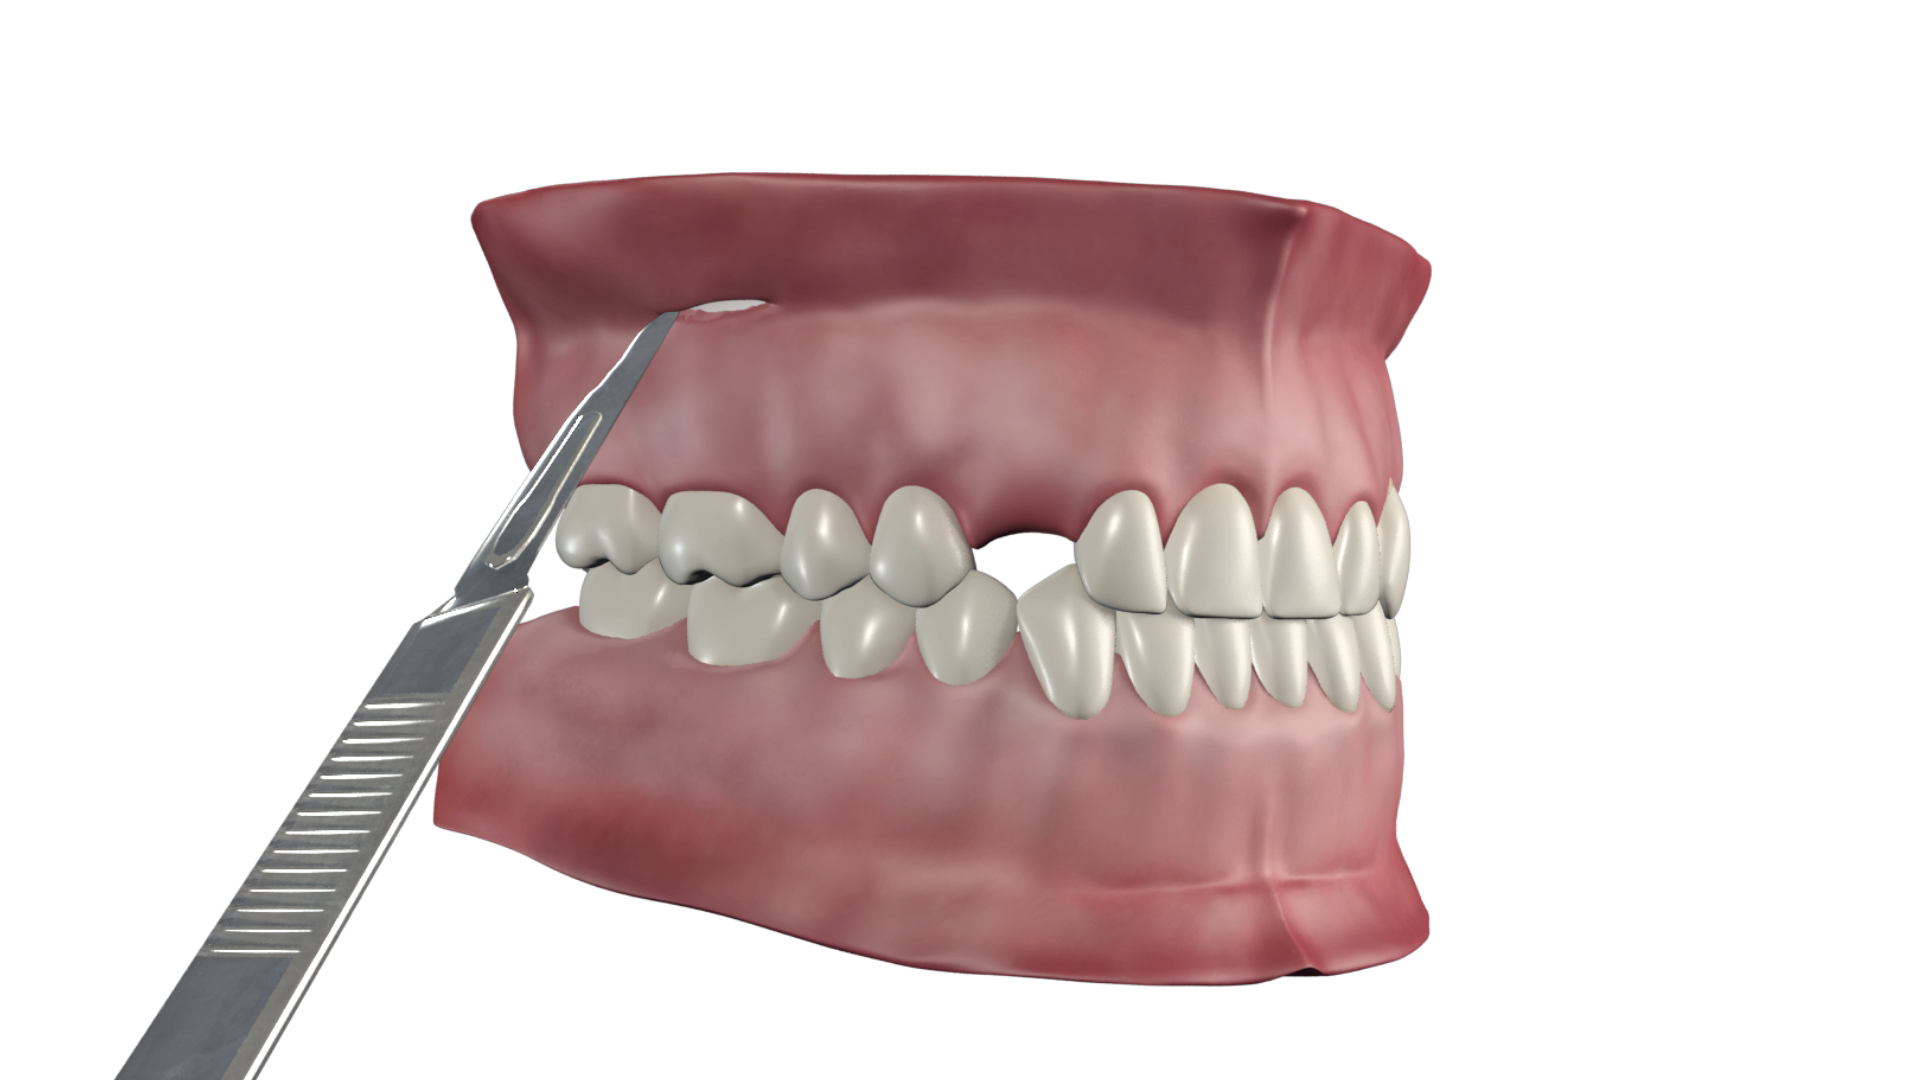

- Incision

Horizontale au bistouri sur environ 10mm le long du repli du fond vestibule, jusqu'au contact osseux.

- Rugination

Sur environ 5mm afin de mettre l’os à nu au-delà des apex pour pouvoir placer la vis.

Note : Dans le cas d’un CT8-2 tunnel, une tunnelisation relie les deux incisions pour permettre de passer un des bras et une boucle sous la muqueuse.

- Réalisation d'une baïonnette au niveau du trait d'incision (fond de vestibule)

En deçà, le fil est plaqué contre l’os, au-delà il doit longer la gencive sans appui.

Elle est réalisée à l’aide de l’instrument dédié dont la gorge coiffe le fil et qui est tourné d’ un huitième à un quart de tour environ afin de compenser l’épaisseur de muqueuse.

Cette manoeuvre apparaît à l’usage la plus délicate à réaliser de toute la procédure de mise en place d’un CT8 car un fil trop écarté gênera à la longue la muqueuse labiale ou jugale, alors qu’un fil trop serré comprimera la gencive d’une manière excessive.

- Pas de suture !

La pression musculaire naturelle des joues et de lèvres suffit amplement pour permettre une bonne coaptation des berges de la plaie, excepté parfois au bord antérieur de la branche montante où la muqueuse peut être plus lâche.